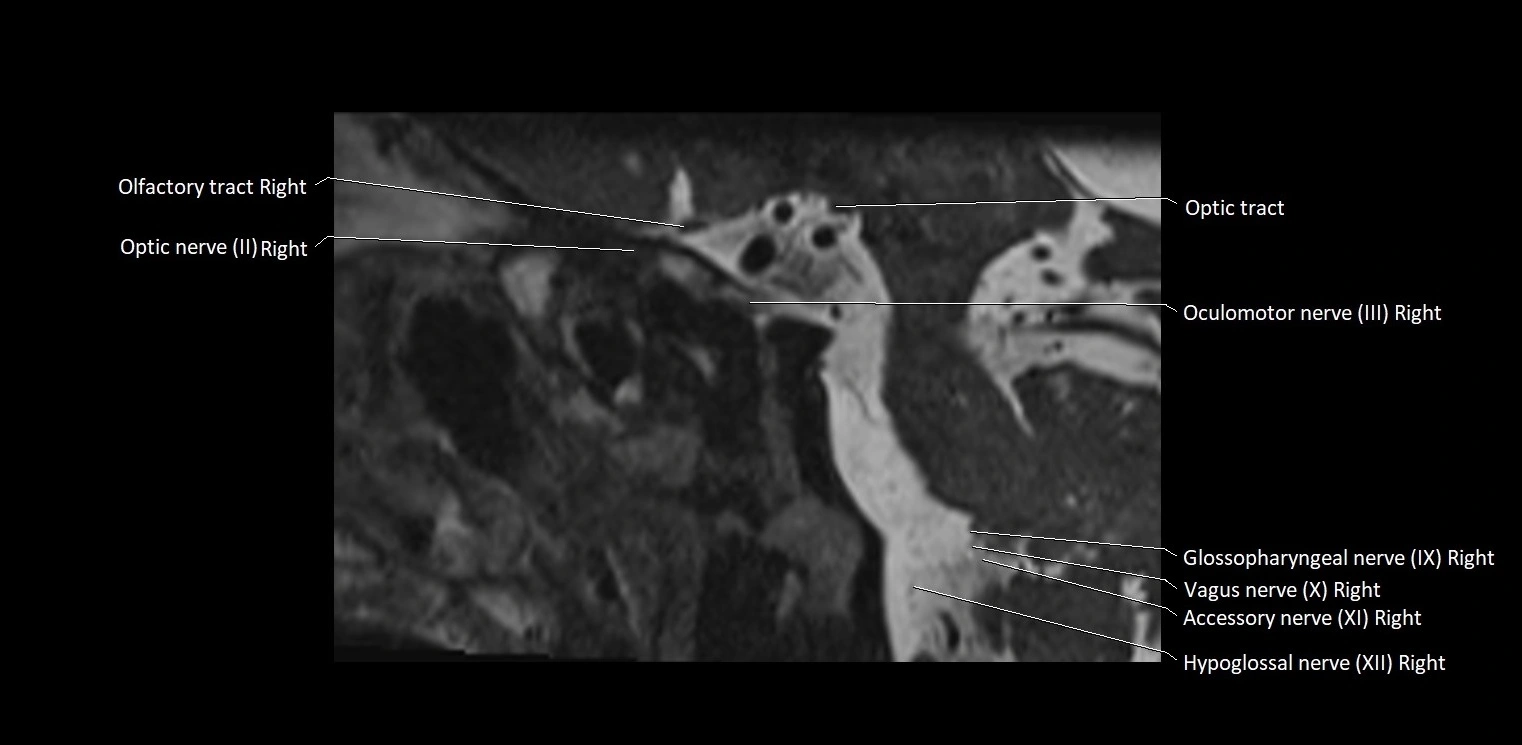

MRI Appearance

• The abducens nerve is a small, thin, linear structure

• Best visualized on high-resolution T2-weighted 3D MRI sequences (e.g., FIESTA or CISS)

• Seen as a hypointense (dark) line running from the brainstem at the pontomedullary junction, traversing the prepontine cistern, and entering Dorello’s canal under the petrosphenoidal ligament, then into the cavernous sinus, and finally the orbit

• May be challenging to visualize in standard MRI due to its small size

• Pathology may be inferred by absence, displacement, or enhancement of the nerve

MRI images

image